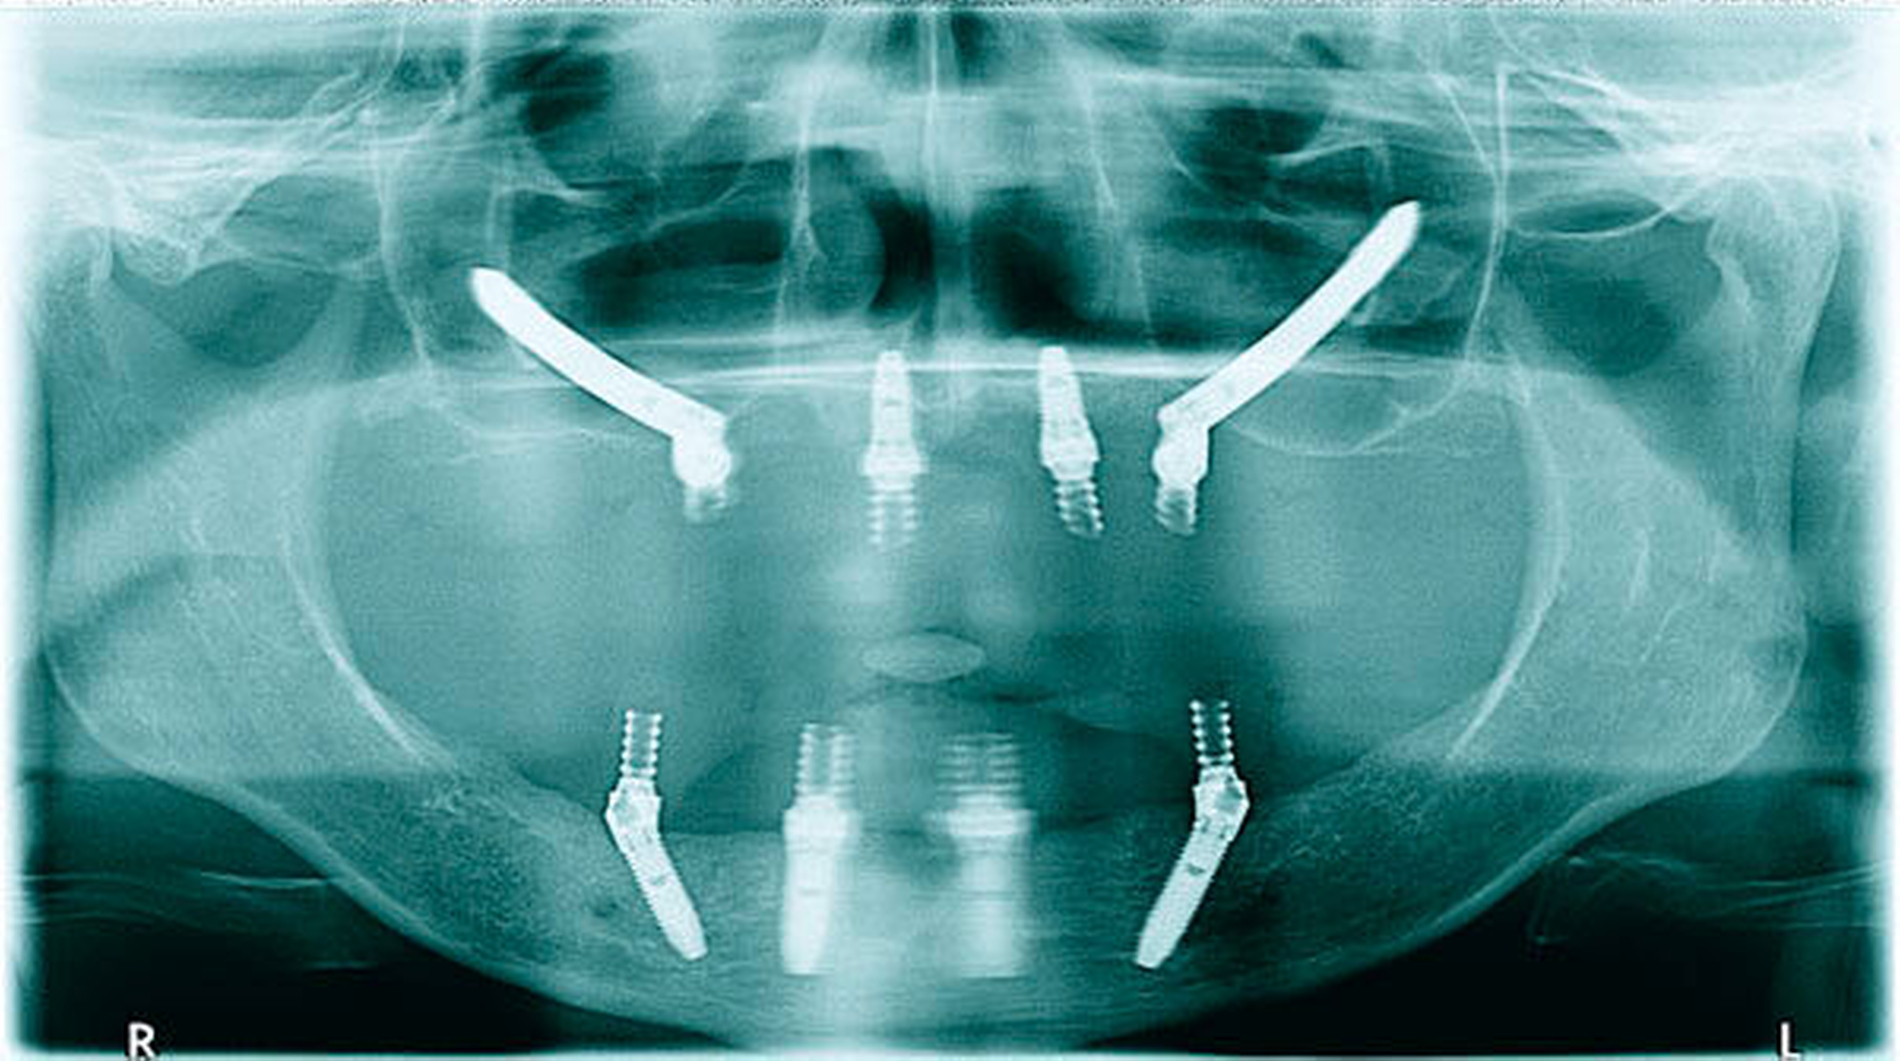

Die in diesem Artikel beschriebene Methode zur Sofortversorgung ganzer Kiefer mit festsitzendem, implantatgetragenem Zahnersatz wurde 1993 in der MaloClinic in Lissabon zum ersten Mal durchgeführt. 1998 wurde diese Vorgehensweise unter der Bezeichnung „All on 4“ als standardisiertes Protokoll für den Unterkiefer eingeführt. Nach der Entwicklung spezieller Implantattypen mit höherer primärer Stabilität wurde diese Vorgehensweise ab 2001 auch für den Oberkiefer angewendet. Um die Anwendung dieser Methode auch im hoch atrophen Oberkiefer zu ermöglichen, wurde die Verwendung von Zygoma-Implantaten ab 2004 mit in diese Methode integriert und das Design der Zygoma-Implantate an die besonderen Erfordernisse angepasst.

Das besondere Kennzeichen dieser Methode ist die Winkelung der distalen Implantate – mit dem Ziel, eine Verankerung eines möglichst langen Implantats im ortständigen Knochen sowie eine möglichst große Unterstützungsfläche für die Suprakonstruktion zu erreichen. Dies gibt die Möglichkeit zur Erreichung einer hohen primären Stabilität (min 30 Ncm), die als Voraussetzung für eine Sofortversorgung- und -belastung erforderlich ist. Die Länge der Freienden und somit die Belastung der distalen Implantate wird durch diese Vorgehensweise verringert.

Die All-on-4-Methode ist eine Möglichkeit zur Versorgung eines gesamten Kiefers mit festsitzendem Zahnersatz. Demzufolge ist die Indikation dann gegeben, wenn ein zahnloser Patient oder ein Patient mit nicht erhaltungswürdiger Restbezahnung eine festsitzende Versorgung wünscht. Für eine Standard-All-on-4-Versorgung ist eine minimale Knochenhöhe von 10 mm bei einer Breite von 5 mm im Bereich von 14 bis 24 beziehungsweise 34 bis 44 erforderlich. Die distalen Implantate sollten einen Durchmesser von 4 mm nicht unterschreiten. Vor diesem Hintergrund ist zur präimplantologischen Diagnostik im Vorfeld eine 3-D-Untersuchung erforderlich. Werden die genannten Voraussetzungen nicht erreicht, kann die Option einer Hybdrid-All-on-4- oder Double-Zygoma-Versorgung mit dem Patienten diskutiert werden (siehe unten). Die dabei notwendige Verankerung der Implantate im Os zygomaticum wurde erstmalig von Brånemark beschrieben und untersucht [Brånemark et al., 2004], später von Stella [Stella and Warner, 2000] modifiziert und von Malo als extramaxilläre Technik weiterentwickelt [Malo et al., 2008].

Die All-on-4-Methode ist eine umfassende Vorgehensweise zur Versorgung unbezahnter Kiefer. Liegen die Voraussetzungen zur Durchführung einer Standard-Operation nicht vor, kann bei einer Knochenhöhe ab etwa 8 mm im Bereich 13 bis 23 eine Hybrid-All-on-4-Versorgung mit jeweils einem Zygoma-Implantat auf jeder Seite durchgeführt werden (Abbildung 5). Hierfür kommen seit Kurzem Zygoma-Implantate zum Einsatz, die nur im unteren Drittel Gewindegänge aufweisen. Dies schafft die Voraussetzung, das Implantat mit der Schulter möglichst weit nach buccal zu positionieren, was die Grundlage für eine hygienefähige Basis einer festsitzenden Versorgung ist. Die oberen zwei Drittel des Implantats (von der Implantatschulter aus betrachtet) sind nur durch Weichgewebe bedeckt (Abbildung 6). Wenn auch im Frontbereich die Knochenhöhe unter 8 mm liegt, besteht die Option für das Double-Zygoma-Verfahren mit jeweils zwei Zygoma-Implantaten pro Kieferhälfte. Die Grenzen dieser beiden technisch anspruchsvollen Vorgehensweisen liegen in der Anatomie des Jochbeins sowie des Oberkiefers (unter Umständen kommt es zur Limitation durch eine zu starke Konkavität im Bereich des lateralen Oberkiefers oder durch ein zu geringes Volumen des Jochbeinkomplexes). Im hoch atrophen Unterkiefer kann die Gefahr einer iatrogenen (postimplantologischen) Fraktur die Methode limitieren.